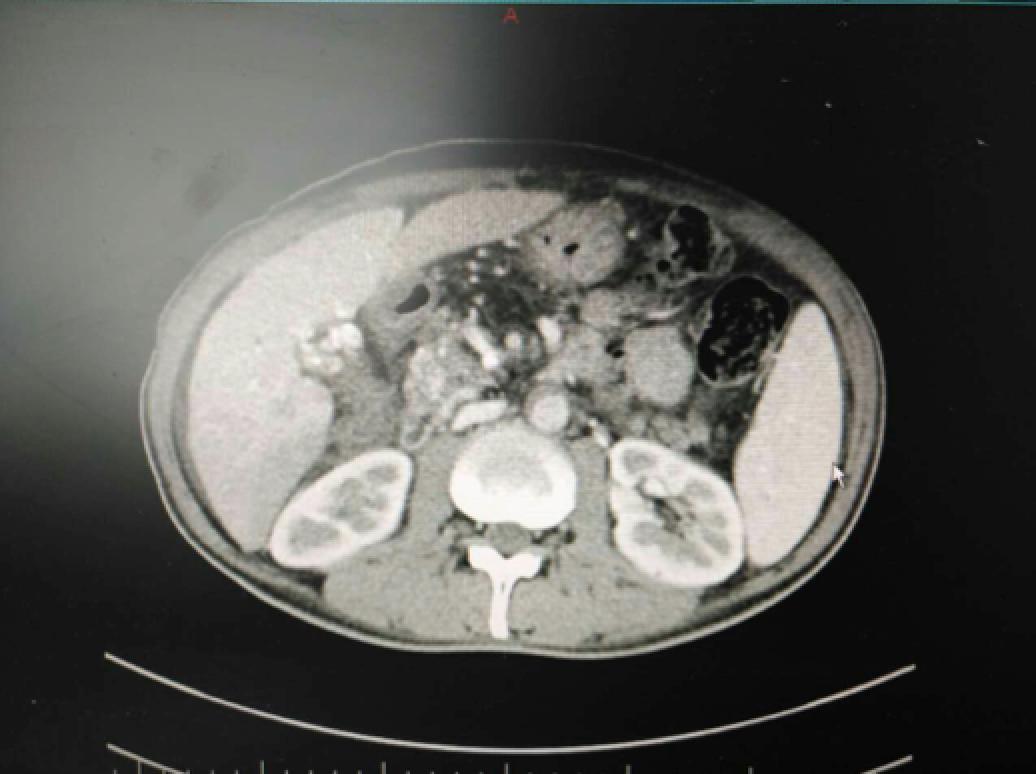

患者因纳差、烧心、腹痛、腹胀2月,于2016-01-17在某县人民医院行腹部CT示肝癌并门脉癌栓形成。分别于2016-01-22、2016-02-19于某市医院行两次TACE术(具体不详)。患者介入术后规律服用抗乙肝病毒、保肝、提高免疫力等药物治疗。2016-02-03至2016-04-30在某省立医院行5周期CIK免疫治疗。2016-05-18至2016-05-25于我院行射波刀治疗门静脉癌栓,具体放疗计划为:42Gy/7F。2016-06-24在我院行肝右动脉化疗栓塞术+肝右动脉灌注化疗术+间接门脉灌注化疗术,术中化疗总量,吡柔比星2mg、顺铂12mg、氟尿嘧啶250mg。分别于2016-05-10、2016-05-27、2016-06-13、2016-07-01、2016-07-27、2016-08-22、2016-09-19、2016-10-07、2016-10-19、2016-11-18、2016-12-18、2017-02-18行12周期免疫治疗。自2016-05-12起患者间断口服靶向药物阿帕替尼250-500mg/d,血压维持在220-130/95-70mmHg,血压升高期间伴上腹部不适,左侧为著,并向腰背部放射,偶尔反酸、烧心,剑突下疼痛,口服抑酸剂或进食后缓解,临床诊断为十二指肠溃疡,目前口服奥美拉唑、马来酸依那普利、氢氯噻嗪等药物对症降压。2017-03-02于我院行第二次肝右动脉化疗栓塞术+肝右动脉灌注化疗术+间接门脉造影术+肠系膜上动脉灌注化疗术。术中化疗总量,洛铂10mg、氟尿嘧啶500mg、吉西他滨400mg。目前间或皮下注射胸腺法新、重组人干扰素α-2b提高免疫力及慢性乙型病毒性肝炎治疗效果。

患者相关影像资料